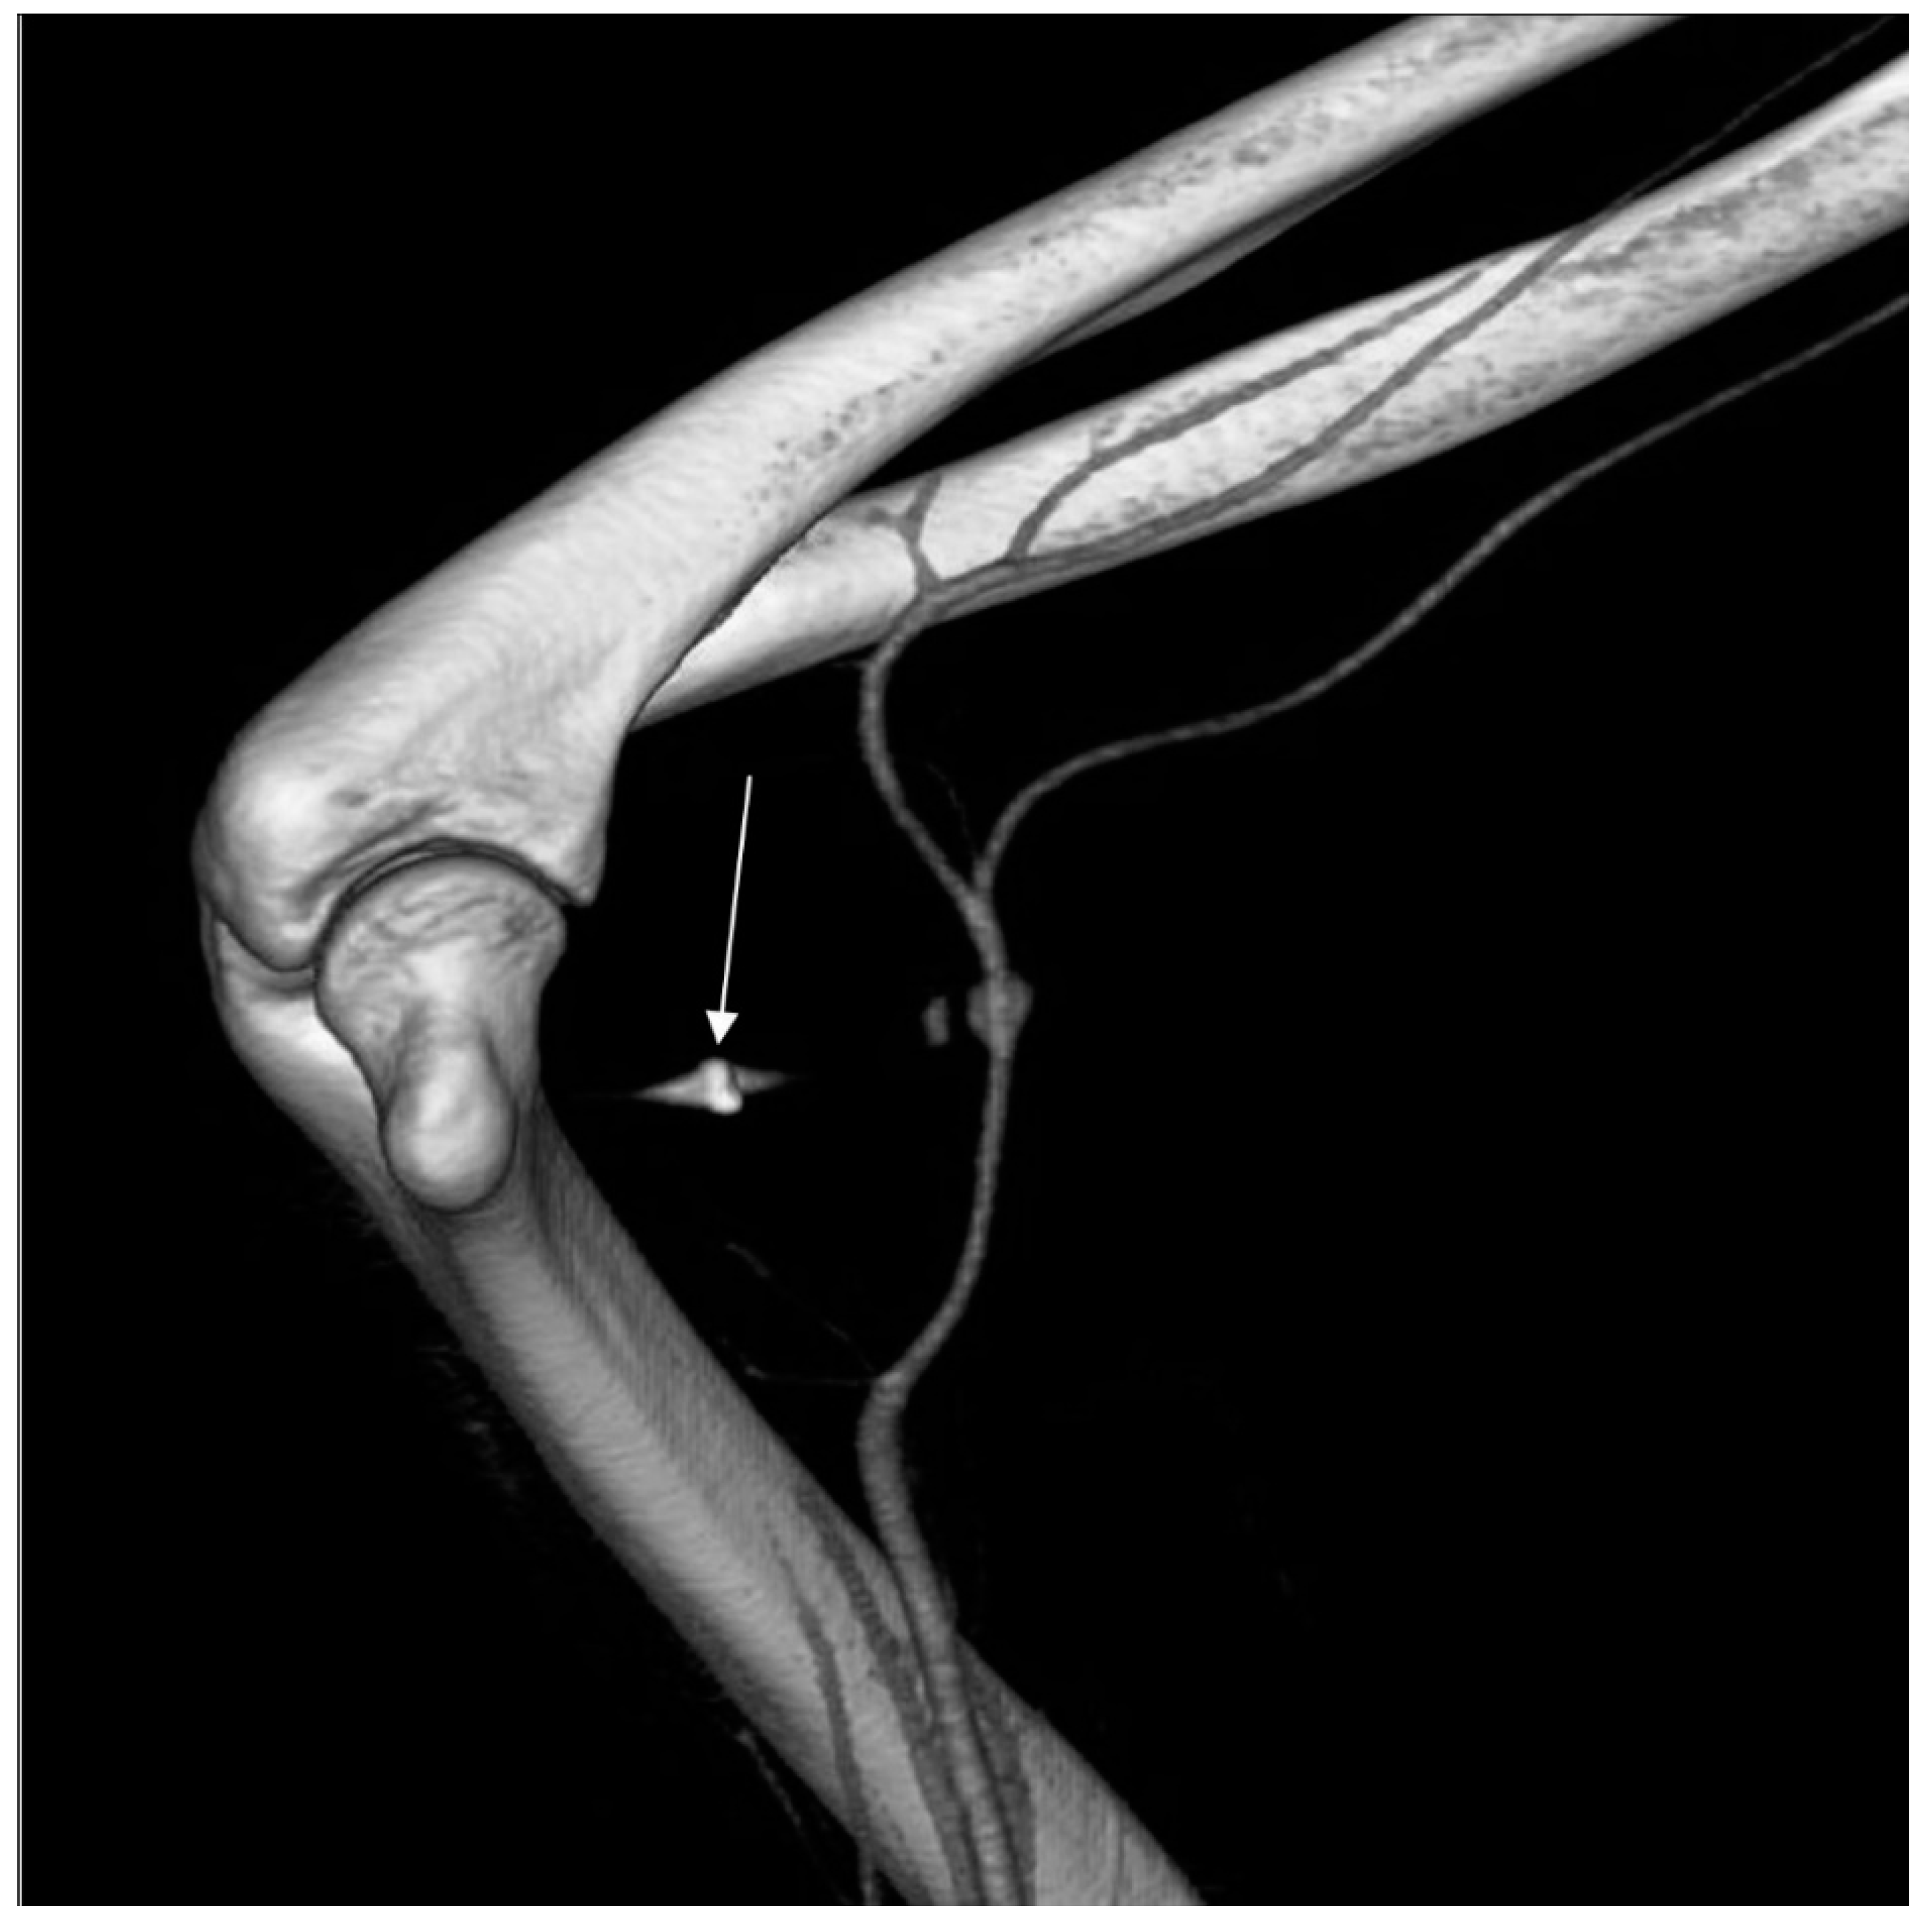

Computed tomography angiography (CTA) of the right upper limb was performed in 5.0- and 0.5-mm layers. The examination showed a non-dilated aortic arch with an independent left vertebral artery ostium between the ostia of the left common carotid artery and the left subclavian artery (Figure 1). Moreover, non-dilated arterial vessels of the right upper limb were visualized—the brachiocephalic trunk, the right subclavian artery, the right axillary artery, the right brachial artery, and the arteries of the right forearm. At the level of the distal epiphysis of the right humerus, just before the division of the brachial artery into the arteries of the forearm, a leakage of the contrast agent beyond the lumen was found, consistent with active bleeding from the injured brachial artery (Figure 2). At this level, a layered soft tissue hematoma was visualized around the brachial artery with approximate dimensions of up to 7.0 cm × 5.9 cm in cross-section and 8.4 cm in the longitudinal dimension (Figure 3). Within the soft tissue hematoma, a high-density, metallic foreign body up to about 0.7 cm in cross-sectional dimensions was localized (Figure 4).

Figure 2. Right upper limb computed tomography angiography. MIP reconstruction. Leakage of the contrast agent beyond the lumen was found, consistent with active bleeding from the injured brachial artery.